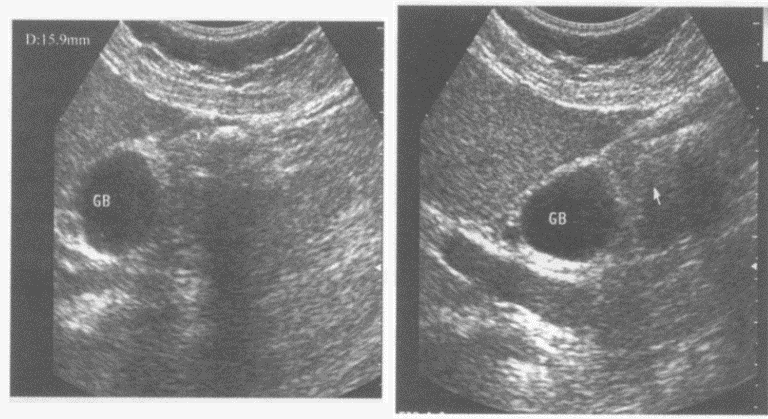

临床资料:女,48岁,右上腹不适。超声综合描述:胆囊壁毛糙,胆囊颈部透声清亮,分隔上胆囊底、体部内未见透声(箭头所示),内可见直径1.6cm弧形强回声光带,后伴声影。

超声提示()

A:胆囊泥沙样结石

B:胆囊息肉

C:胆囊充满型结石

D:胆囊多发结石(分隔上充满型)